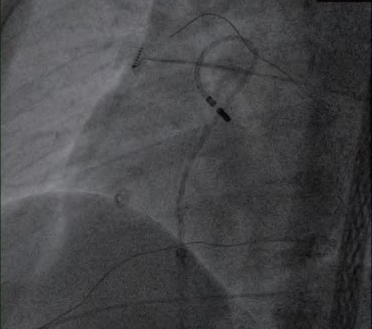

(3)在Carto或Ensite标测系统下实时重建心腔的三维解剖模型,采用激动标测或者起搏标测观察激动顺序颜色的变化,准确标测室早的最早激动部位,寻找消融靶点。放电消融直至室早终止(图2-3-1)。

图2-3-1 股静脉入路行右心室来源室早消融